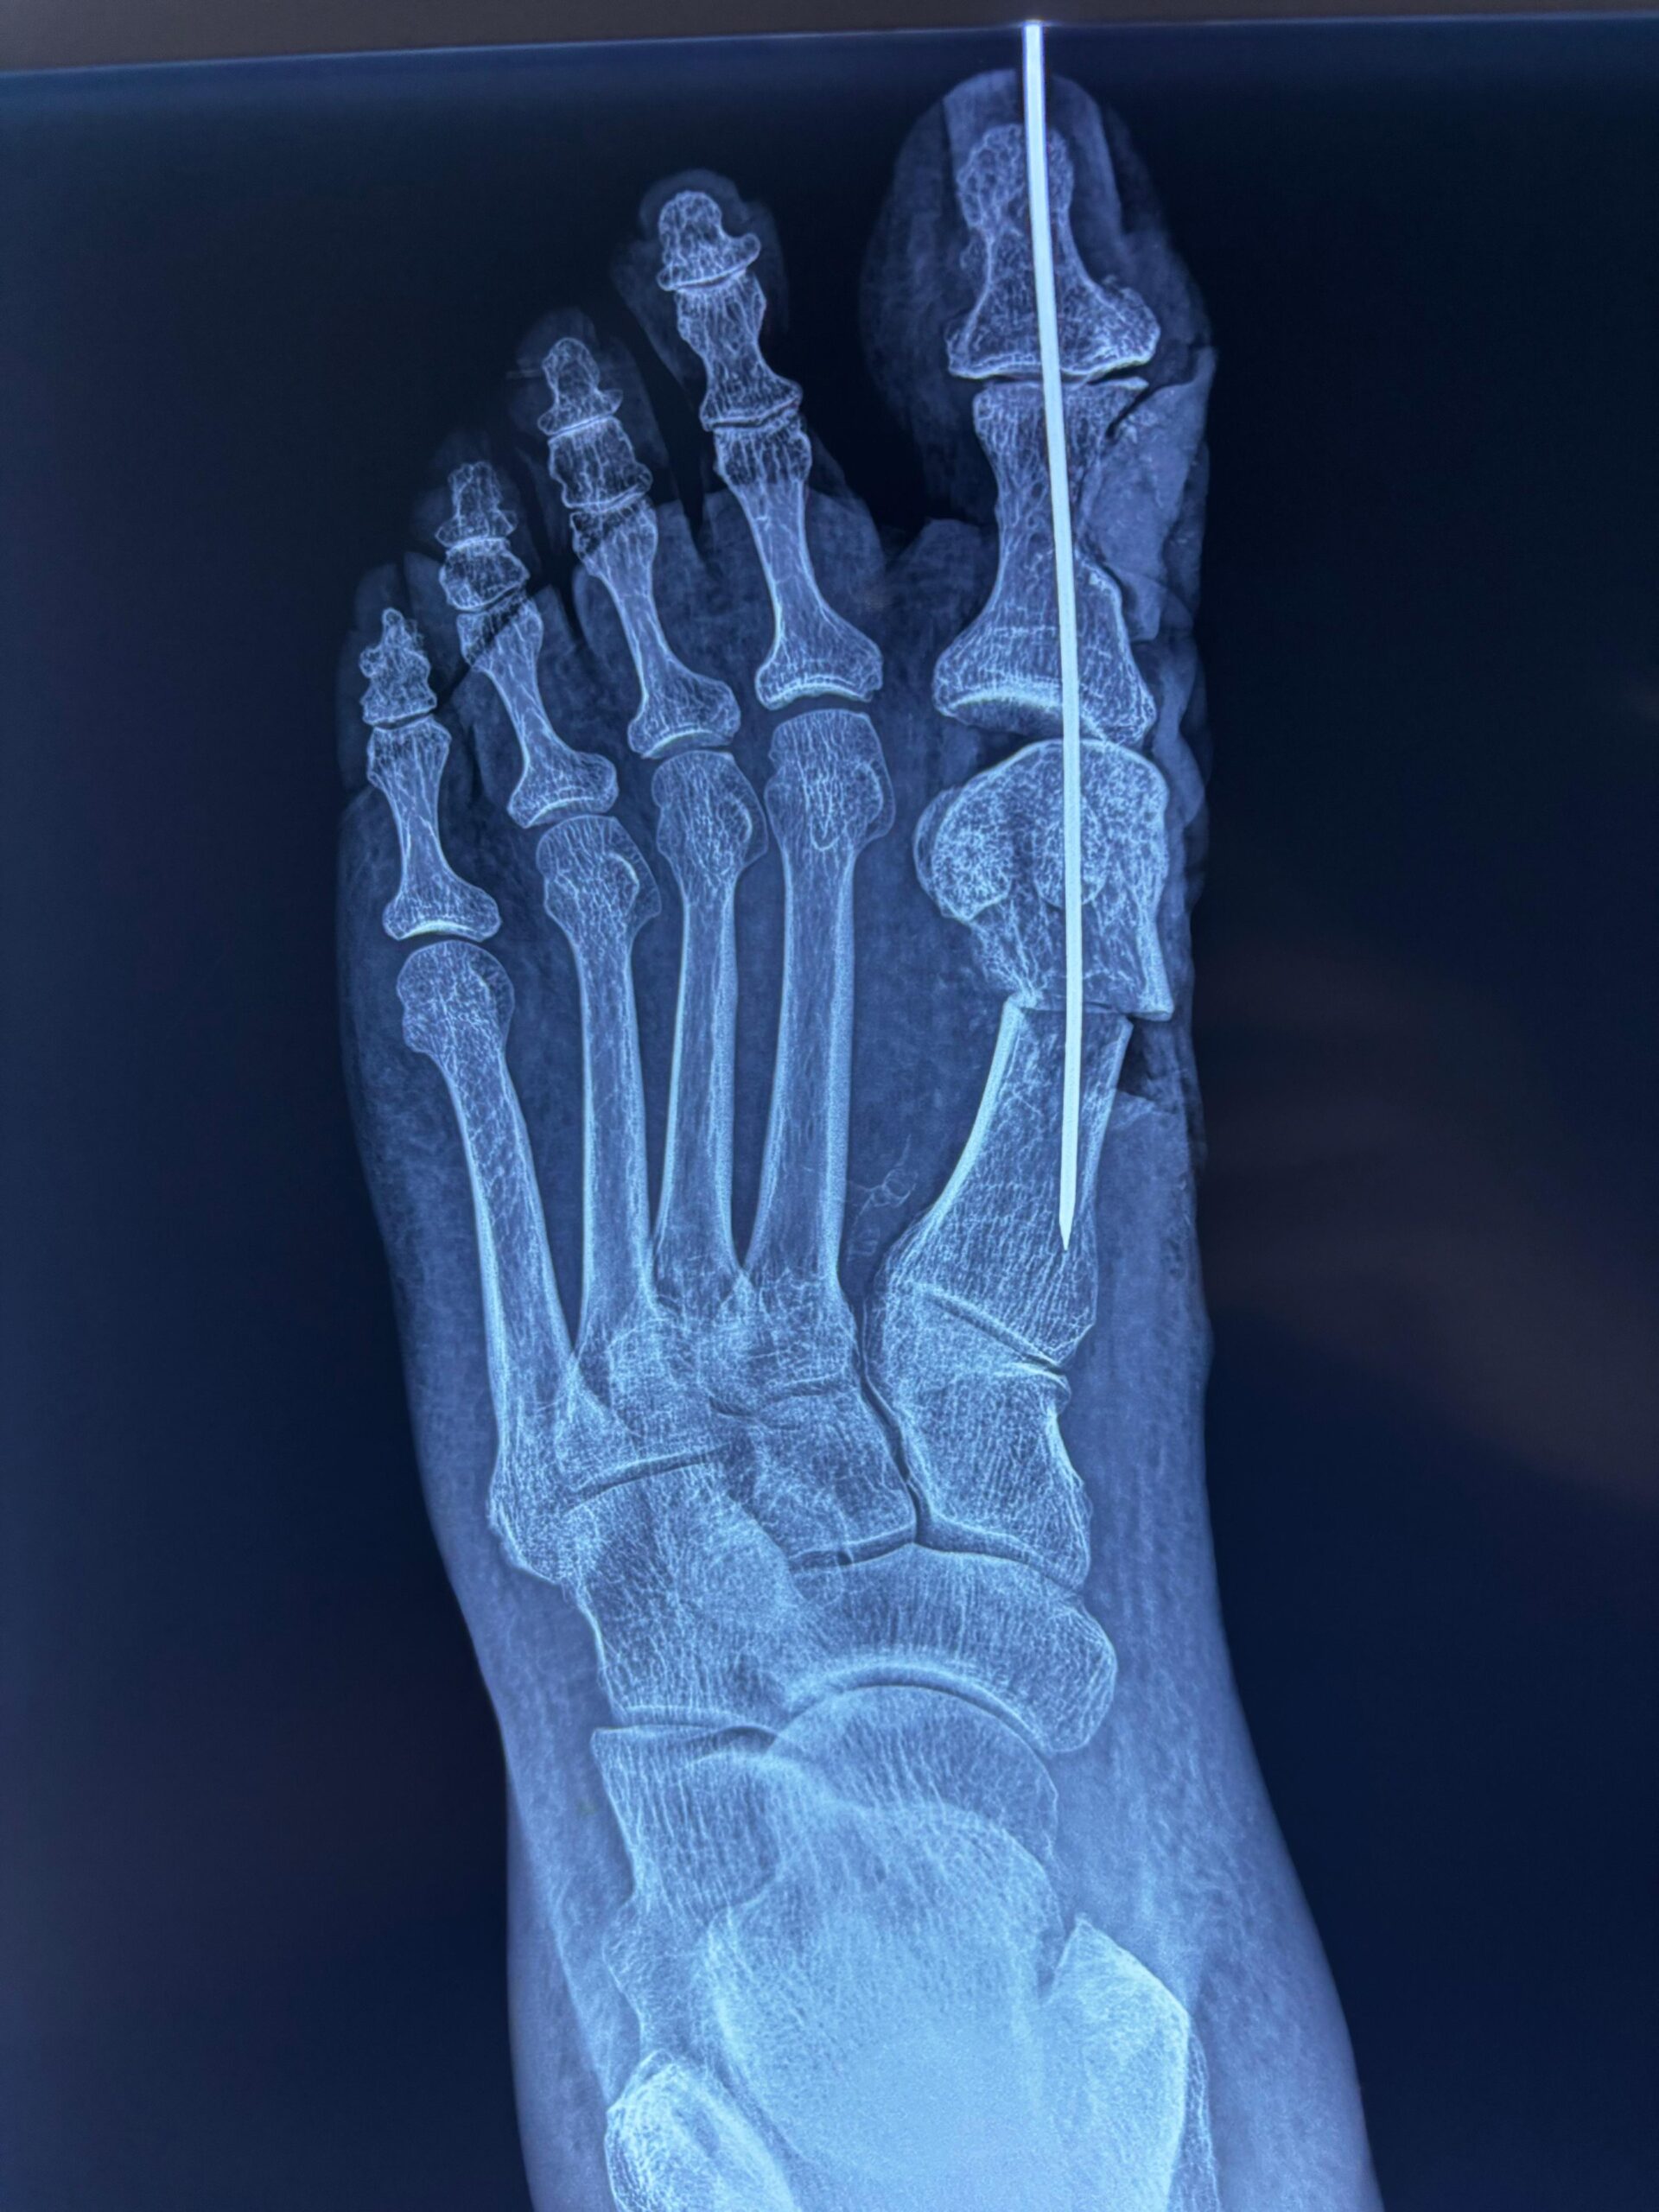

Deformidades digitales y hallux valgus

Artroscopía y cirugía mínimamente invasiva